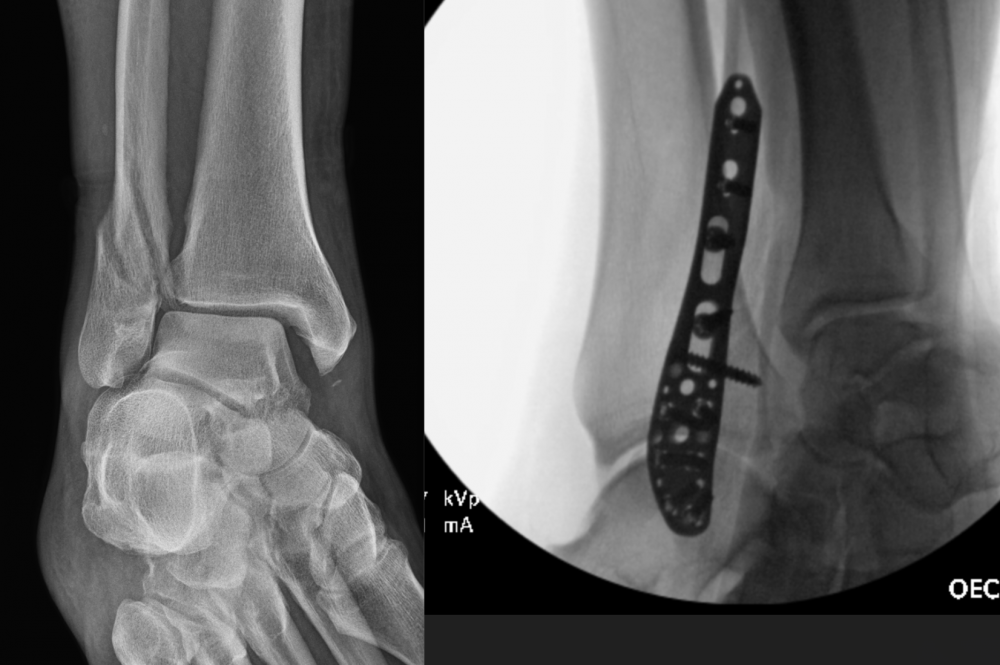

Ug, yeah sucks as sometimes might have to get it taken back out. I had plate in ankle when snapped it in 2 places mid Dec. It just wasn't healing up right and was uncomfortable, ankle like concrete by end of day. Had it removed little over a week ago, 7/7 - better, should finally heal up for good and feels lot better. Should have done it couple months ago but kept hoping, but after 6 months of keeping gauze on it and compressing it, I had enough. He told my wife after surgery that it was getting infected under the plate. But also had the plate where not much fat or meat so it was like my skin stretched over plate where pulled apart from swelling after staples removed that f'd up my initial healing process - but plate gone now and stitches come out this Friday.

But really hoping none of those troubles, prob exacerbated by being at lowest part of body where i couldnt lay in bed all day to keep from swelling.